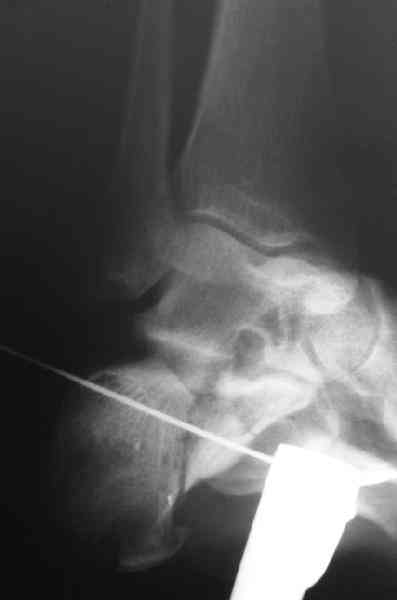

Re: Перелом пяточной кости

Какой предпочитаете доступ? Нет ли показательных рентгенснимков?

Открытый и закрытый способы лечения.